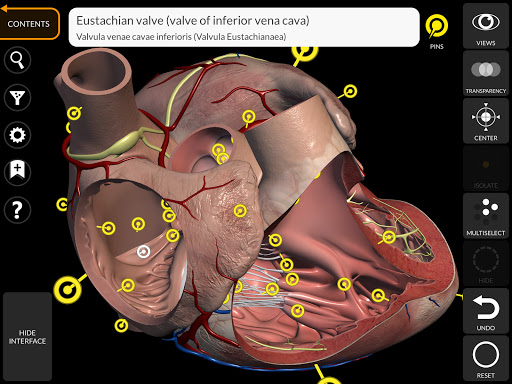

يتيح لك "Anatomy 3D Atlas" دراسة التشريح البشري بطريقة سهلة وتفاعلية.

من خلال واجهة بسيطة وبديهية، من الممكن ملاحظة كل بنية تشريحية من أي زاوية.

تتميز النماذج التشريحية ثلاثية الأبعاد بتفاصيل خاصة ودقة تصل إلى 4K.

• الجهاز القلبي الوعائي

• خيار إخفاء أو عزل نموذج واحد أو نماذج متعددة مختارة

• من خلال تحديد نموذج أو دبوس، يظهر المصطلح التشريحي ذي الصلة

• وصف العضلات: الأصل والإدخال والتعصيب والعمل